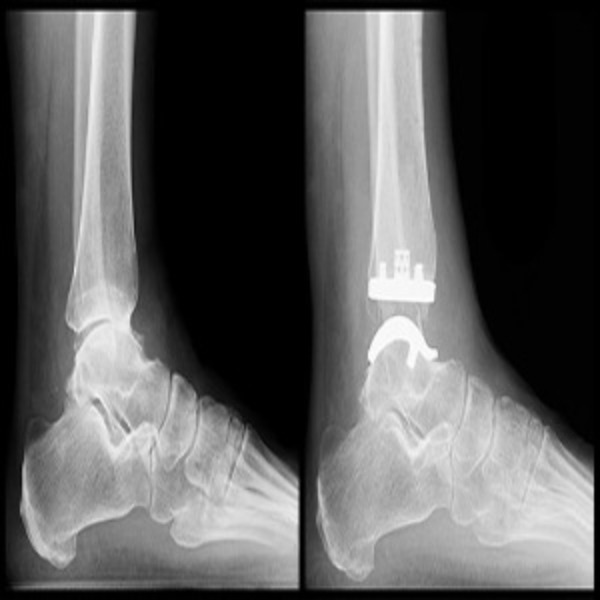

Expert Orthopedic Surgery with Compassionate Care